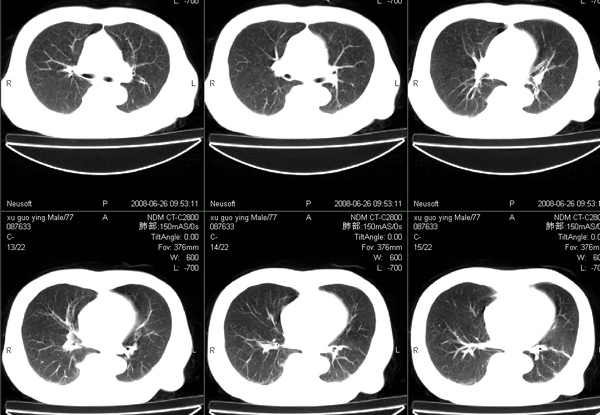

以下是引用狙击手在2008-6-26 20:16:00的发言:[br]上腹部除了胆囊大一点,其余未见明显异常,肺尖部见纤维条索样影,左肺下叶见空洞样占位,壁较厚,临近胸膜见牵拉,周围未见卫星灶,考虑:1:左下肺周围性肺癌;2:肺尖部陈旧性结合灶。

以下是引用liuqiang在2008-6-26 21:11:00的发言:[br]上腹部除了胆囊大一点,其余未见明显异常,肺尖部见纤维条索样影,左肺下叶见空洞样占位,壁较厚,临近胸膜见牵拉,周围未见卫星灶,考虑:1:左下肺周围性肺癌;2:肺尖部陈旧性j结核灶。